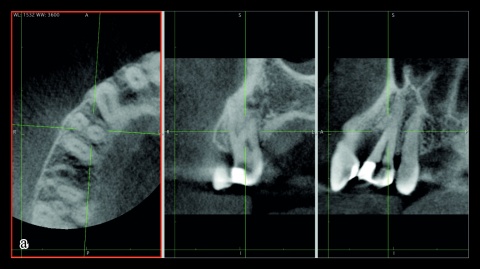

Die übersichtliche Anordnung der wichtigsten Parameter in einem Zahnschema, das unter prothetischen Aspekten zusammengestellt wurde, erleichtert in Zusammenschau mit dem bewertenden Ampelschema (Abb. 4) auf einer Panoramaschichtaufnahme die Entscheidungsfindung erheblich [13] und objektiviert die Einschätzung des Zahnes bezüglich seiner Wertigkeit als Pfeiler.

Hier spielt das spätere Behandlungskonzept eine wesentliche Rolle. So ist zum Beispiel die Integration stark gekippter Pfeiler in einer Modellgussklammerprothese sowohl konstruktiv schwierig, als auch wenig sinnvoll. Bei der Durchführung des Konzeptes der totalen Pfeilerintegration, wie in Abbildung 5 dargestellt, kann aber beispielsweise durch die Fassung des stark gekippten Zahnes in einem Doppelkronensystem eine weitere Kippung vermieden werden. Der Erhalt des endständigen, wenn auch gekippten Zahnes verbessert wiederum die Lagestabilität der Prothese signifikant. Auch als endständiger Brückenzahn kann ein solcher, in seiner Wertigkeit reduzierter, Pfeiler bei ansonsten guten parodontalen Parametern gute Dienste leisten und eine Freiendsituation vermeiden.

- Foto 2 – 5 : Bildarchiv von Prof. Dr. Peter Pospiech.